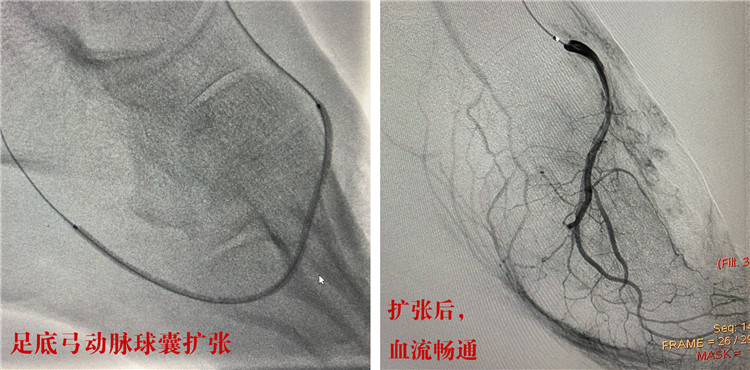

首先,由經(jīng)驗豐富的放射科介入團隊成功行下肢動脈硬化血管球囊擴張,血管開通后,陳先生的左下肢血流立刻恢復(fù)暢通;隨后,燒傷科為陳先生切除了左腳的干性壞疽,并給予潰瘍清創(chuàng)及腳面植皮;內(nèi)分泌科全程監(jiān)控,幫助患者控制血糖的同時,耐心換藥護理。